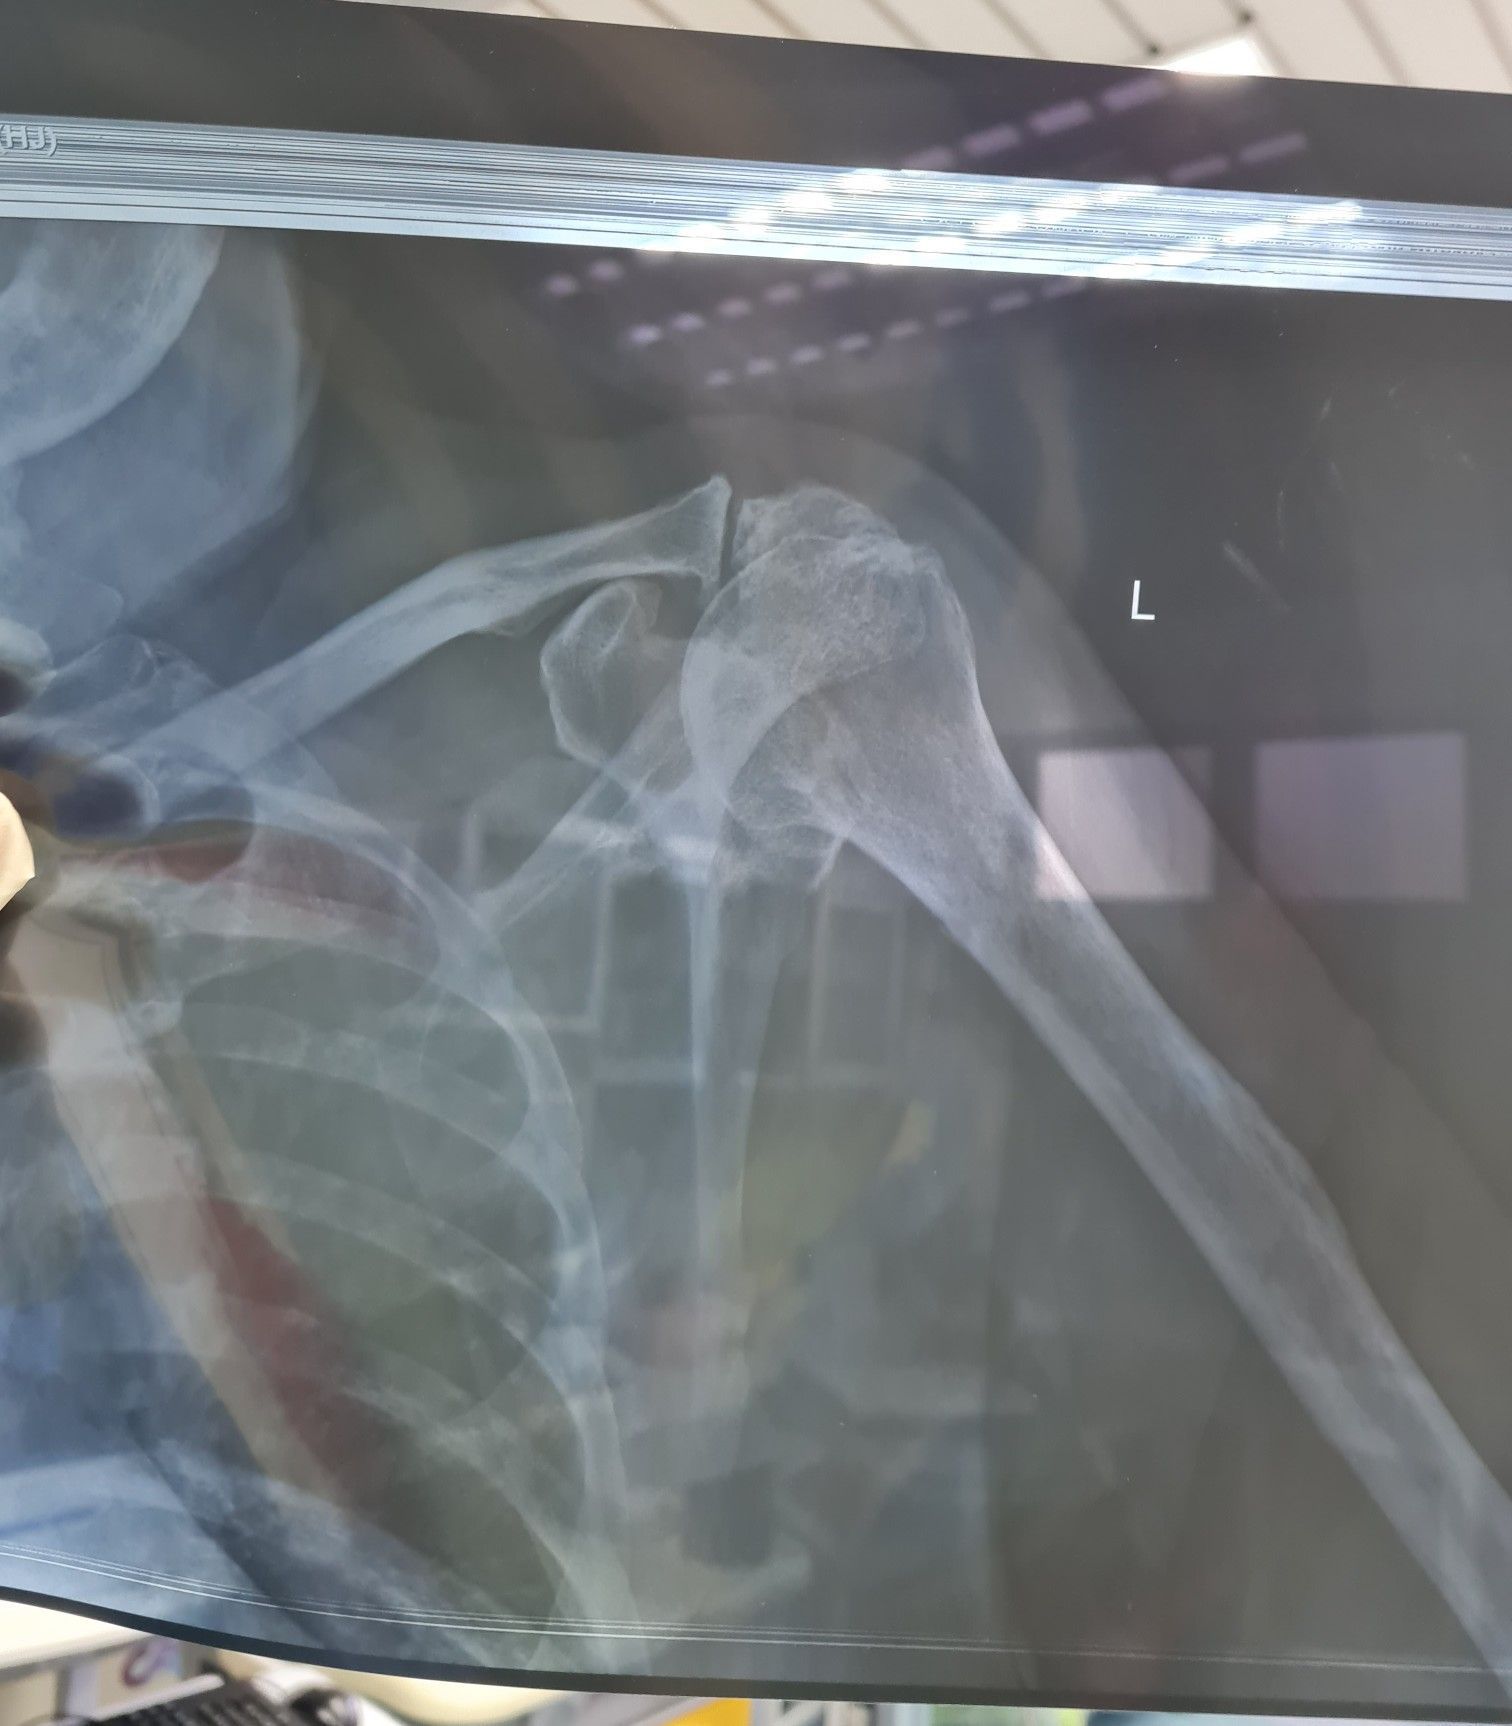

Shoulder xray - need help interpret/analysis.

Sorry about the poor film quality

89yrs old male with regular falls. Chronic anterior shoulder dislocation.